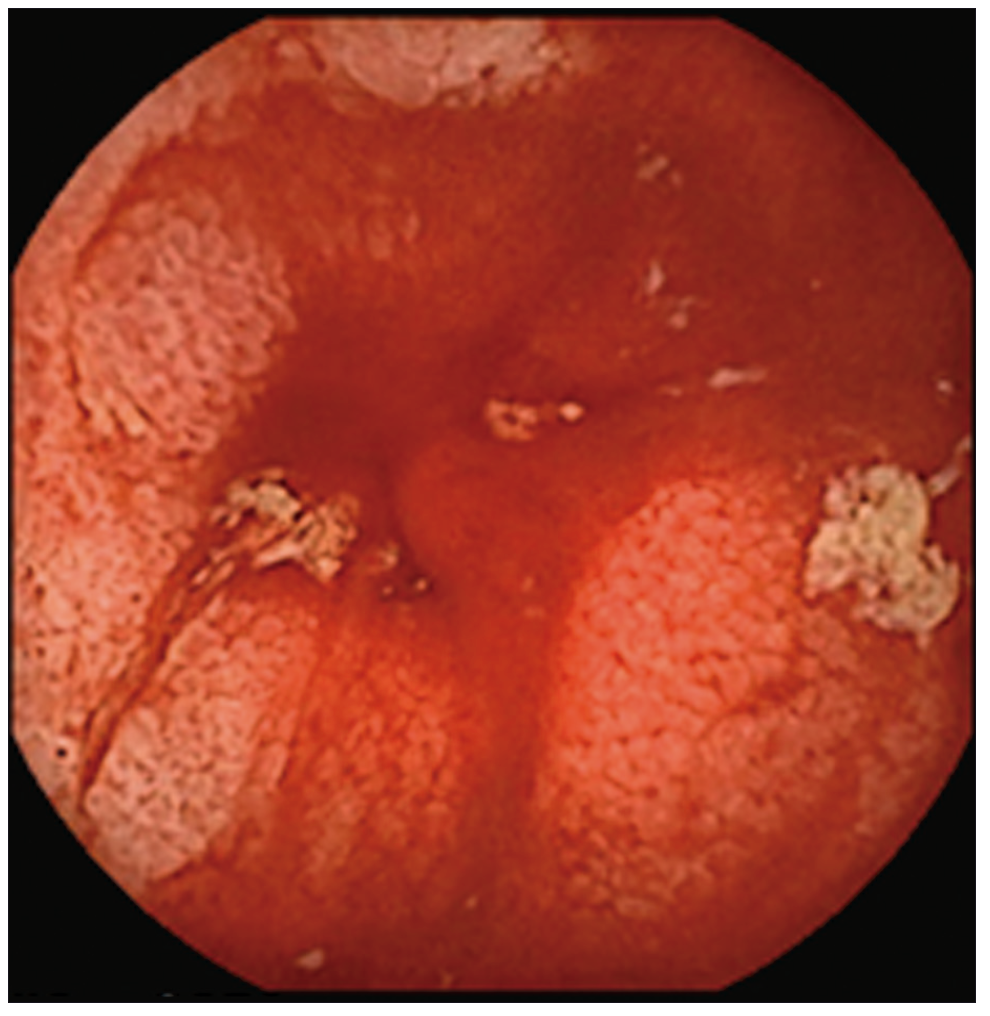

Con respecto a las imágenes, la radiografía directa de abdomen y la telerradiografía de tórax fueron normales. Se realizó una tomografía computada (TC) de abdomen que mostró asas de intestino delgado de paredes engrosadas sin estenosis, ausencia de líquido libre y presencia de divertículos en el colon. Se administraron hidratación y alimentación parenterales, y dos transfusiones de sangre. Se solicitó una videoendoscopía digestiva alta que evidenció gastropatía antral. En la videocolonoscopía hasta ciego se observó diverticulosis sigmoidea. Se constató la presencia de sangre fresca a través de la válvula íleocecal pero no se logró canular el íleon. Se solicitó una cápsula endoscópica (CE) donde se observó la presencia de sangre fresca y coágulos desde el yeyuno medio hasta íleon, con múltiples úlceras lineales, cicatrices y vasos de neo formación que alternaban con mucosa de aspecto normal (Figuras 1-3).

Figura 3. Sangrado activo

Las zonas afectadas presentaban disminución del calibre de la luz intestinal. Dichos hallazgos eran compatibles con enfermedad de Crohn. No se observó el pasaje de la cápsula a colon a través de la válvula íleo cecal.